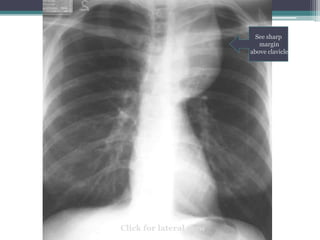

Which compartment do you think this mass is in?

Click for answer

Mass

โ€œdisappearsโ€

at clavicle

Cervicothoracic sign

โ€ข Answer: Mass lies in anterior mediastinum. We

know this because it disappears at the level of the

clavicle where it extends into the neck.

โ€ข This particular example is Non-Hodgkins lymphoma